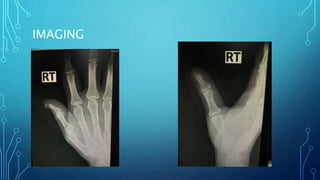

IMAGING

DIAGNOSIS

• Open fracture distal phalanx of Rt. Thumb with nail bed injury